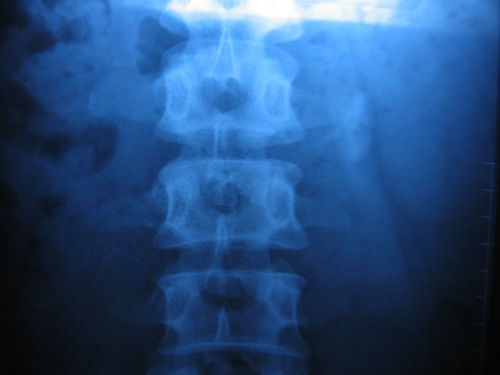

当您或您身边的人出现类似艾滋病感染的症状时,请务必保持警觉。及时寻求医疗帮助是战胜病魔的关键。去正规医院接受科学的诊断和治疗,您将获得更多的信心和力量。只有通过专业的检测和治疗,我们才能了解病情的真实情况,制定出最适合的治疗方案。